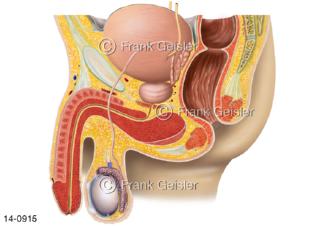

Bildergalerie Urogenitalsystem

Bilder zum Urogenitalsystem mit Urogenitalorgane, Urogenitaltrakt, zum Harn- und Geschlechtsapparat, Harnorgane und Geschlechtsorgane, Organe der Harnwege und der Fortpflanzung, Harnorgane und Geschlechtsorgane im männlichen und weiblichen Urogenitalsystem